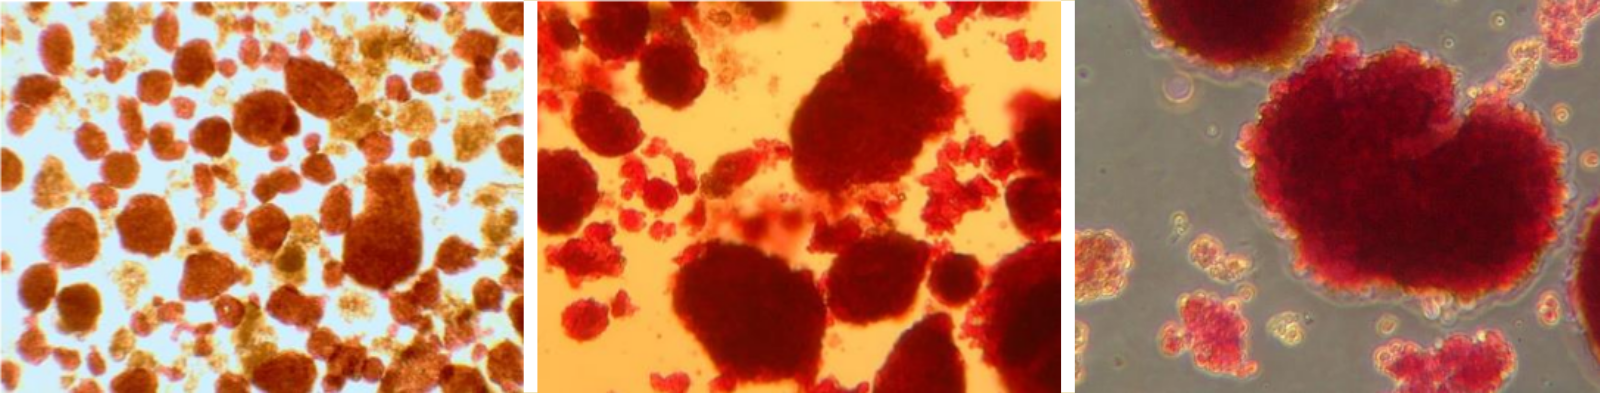

Les îlots sont colorés à la dithizone (chélateur du zinc colorant en rouge la molécule d’insuline). Les îlots de Langerhans sont des amas formés de quelques dizaines à plusieurs milliers de cellules endocrines, dont les cellules β productrices d’insuline (de gauche à droite : ×100, ×200 et ×500).